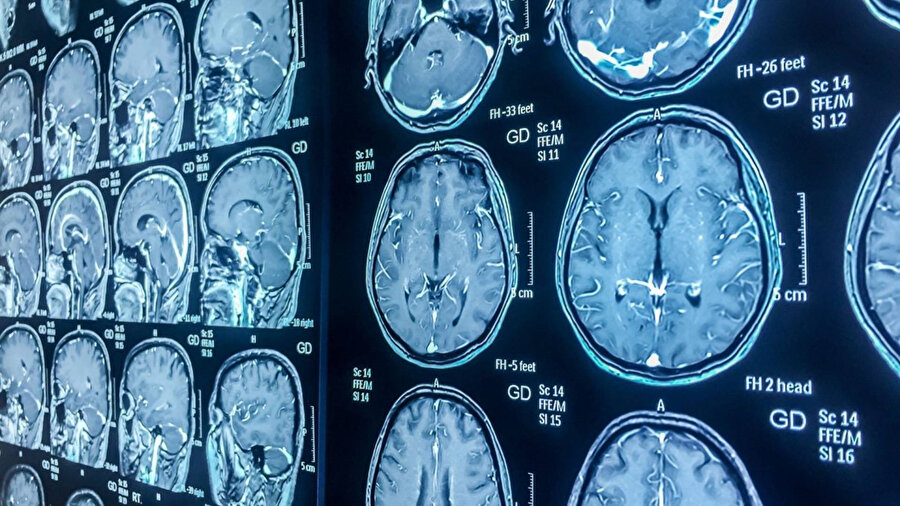

İngiltere’de yürütülen dünyanın en kapsamlı görüntüleme projesi tamamlandı. 100 bin gönüllünün beyin, kalp ve iç organları taranarak hastalıkların erken teşhisi için dev bir veri tabanı oluşturuldu.

Bilim insanları, dünyanın en büyük insan görüntüleme projesi ile 100 bin kişinin beynini, kalbini ve diğer organlarını tarama hedefine ulaştı.

Dev tıbbi görüntüleme projesi, İngiltere'deki dört merkezde haftanın yedi günü, günde 13 saat boyunca devam ediyor. Katılımcılara beş farklı tipte MRI, X-ray ve ultrason makinesi kullanılarak taranmaları için beş saatlik bir randevu veriliyor.